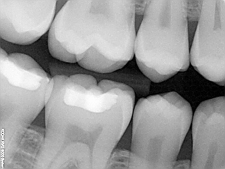

What are Digital X-Rays?

The introduction of digital imaging into the dental field has been one of the most exciting aspects of technology that a dental office can provide. Randolph Dental is proud to use the latest in digital imaging technology.

The introduction of digital imaging into the dental field has been one of the most exciting aspects of technology that a dental office can provide. Randolph Dental is proud to use the latest in digital imaging technology.

Imagine instant imaging onto a computer screen. Couple that with Approximately 75% less radiation exposure and incredible imaging detail with the ability to alter the image to the desired needs of the procedure. Images are easily stored and printed or can be emailed in the event of a referral.